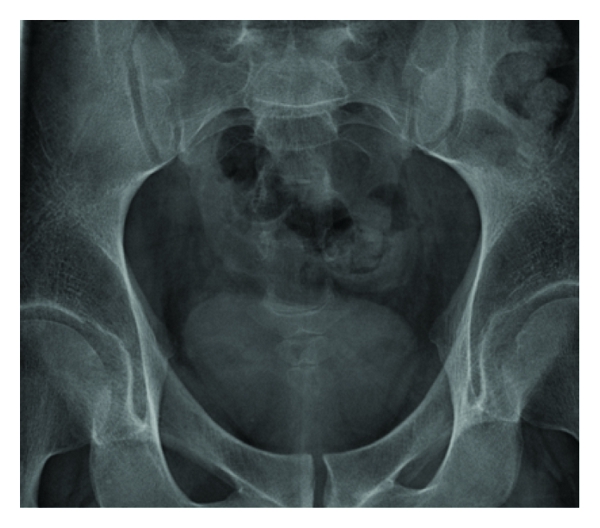

This characteristic difference in attenuation with dual-energy imaging (i.e., contemporaneous CT scanning at 80 and 120−140 Kv) may potentially allow accurate determination of stone composition which may facilitate more appropriate management in patients with uric acid (UA) containing calculi who may benefit from medical management and those with cystine and certain calcium stones which may be more resistant to shock wave lithotripsy [43] (see Figures 2–3).

(a)

(b)

(c)

(d)